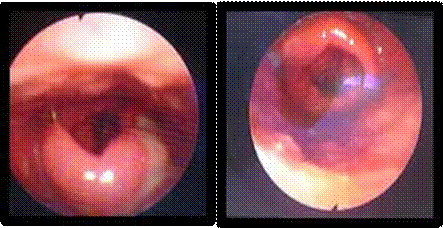

Uvéite Postérieure

L’uvéite postérieure est la manifestation inflammatoire la plus fréquente et la plus grave. Elle est marquée principalement par une hyalite (figure 2), d’intensité variable, pouvant être responsable d’une baisse importante de l’acuité visuelle avec un fond d’œil complètement masqué (4).

Vascularites rétiniennes

La vascularite rétinienne est fréquente. Elle peut être veineuse le plus souvent, mais aussi artérielle et se traduit par des lésions de périphlébites, de périartérites et de thromboses vasculaires (5).

On observe le plus souvent une périphlébite occlusive, caractérisée par un engainement de la paroi veineuse réalisant un aspect de « brume » floconneuse blanchâtre entourant la colonne sanguine. L’atteinte est segmentaire (figure 3).